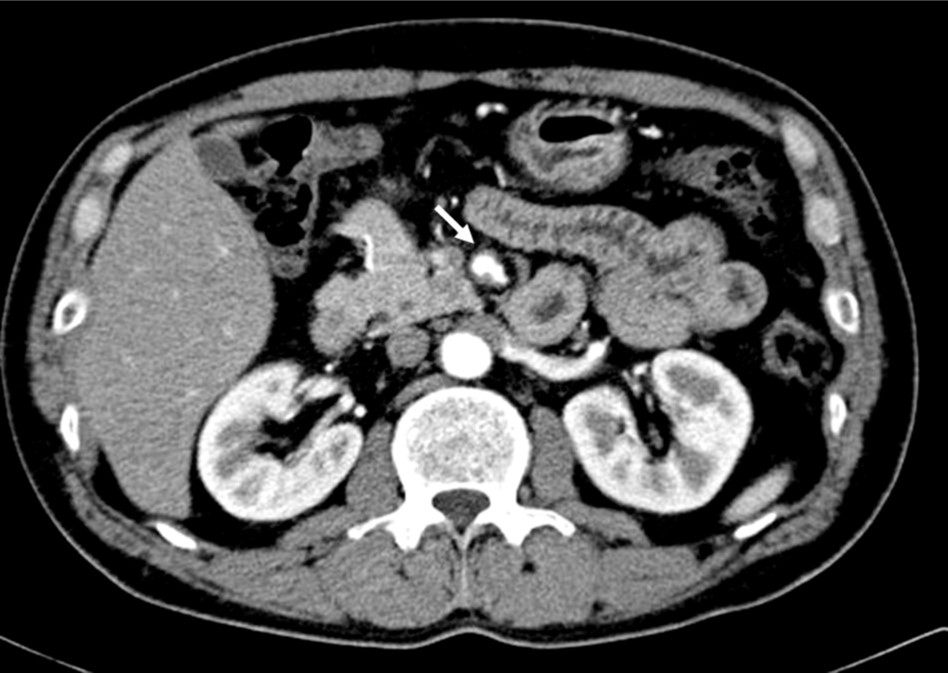

2009년 3월 복부 CT에서 SMA 기시부 하방 2cm 부위부터 5cm 길이의 편심성 혈전이 관찰되고 있으며 혈전이 있는 부위의 동맥 직경이 커져 있음(Fig. 1). 대동맥이나 분지 동맥에 동맥경화증의 소견은 관찰되지 않으며 심장초음파 및 심전도 검사에서 혈전이나 심방 세동은 없었음. CT 소견과 증상을 기준으로 spontaneous isolated SMA dissection으로 진단하였으며 창자의 허혈 소견이 보이지 않고 통증도 악화되지 않아 보존적 치료를 하였음. 2009년 6월 추적 CT에서 false lumen내 대부분의 혈전은 소실되었으나 SMA 기시부 5cm 하방 부위에는 국소적 혈전을 동반한 saccular pseudoaneurysm이 관찰됨. 2009년 8월 시행한 추적 CT에서 pseudoaneurysm의 직경이 2mm 증가함 (Fig. 2). 2009년 9월 시행한 혈관 조영술에서 saccular pseudoaneurysm이 SMA 기시부 5cm 하방부위에 관찰되며 SMA의 국소적 협착이 관찰됨 (Fig. 3). 스텐트와 코일을 이용한 혈관 내 치료 후 시행한 혈관 조영술에서 SMA의 국소적 협착과 pseudoaneurysm은 소실됨 (Fig. 4). 시술 3개 월 후 시행한 추적 CT에서 pseudoaneurysm은 완전히 소실되었으며 SMA는 정상소견을 보임(Fig. 5).

Fig. 1.

Fig. 1. Enhanced CT scan shows eccentric thrombosis in the superior mesenteric artery at the levrd of transition zone from a fixed segment under the pancreas to the mobile segment at the mesenteric root.